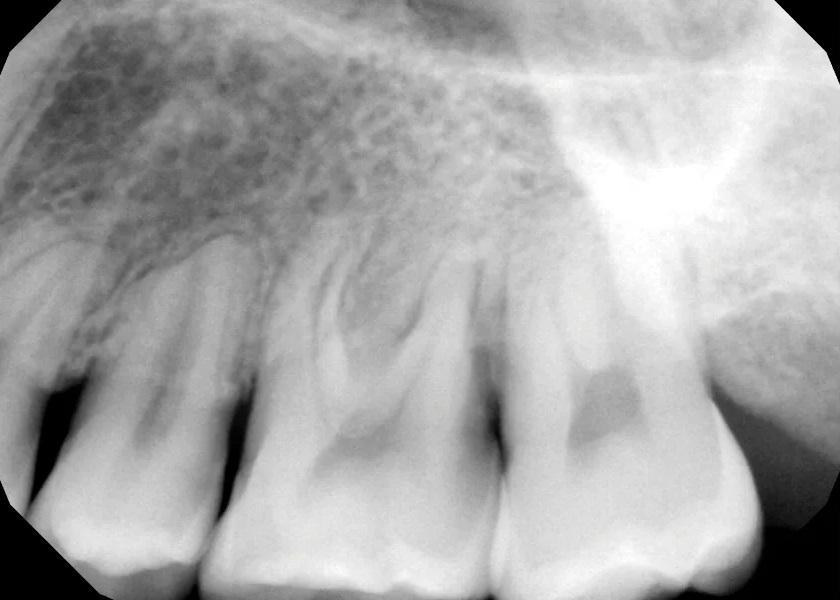

Фото 3. Предоперационный периапикальный рентгеновский снимок, показывающий короткие, затупленные корни зубов № 2.4, с апикальной резорбцией корня зуба № 2.5 и дистального щечного корня зуба № 2.6. Отмечалась тесная близость корней зубов №№ 2.6 и 2.7 с умеренным образованием интерпроксимальных кариозных полостей. Рентгенологическое просветление в основном затрагивало фуркацию зуба № 2.6.